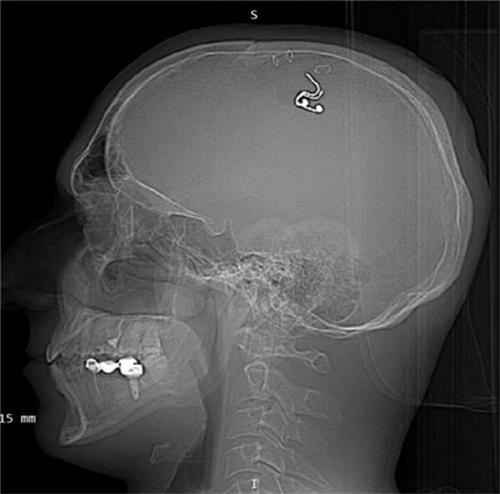

7月23日以及俄羅斯男子為控制夢境在大腦內植入芯片的話題,充上了微博的熱搜,不少網友也對于這一舉動感覺到不可相信。俄羅斯40歲的一名男子邁克爾-拉住加,此前一直在鉆研神經科學等這些領域,近日邁克爾-拉杜加在家中自己做腦部的手術,僅僅進行了半個小時,就失血達到了一升多,仍然將電極成功植入到大腦當中。最后經過設備的觀測,不同睡眠狀態之下有三次夢境情節發生改變的情況出現,也出于對健康的考慮,五周后還是前往醫院將腦中植入的電極移除了